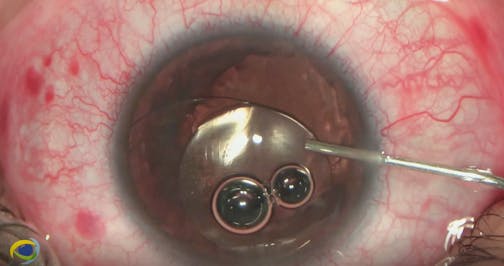

Abdelwahhab Azzawi, MD, FEBO, MRCPS (Glasgow), presents a surgical case in which he performs phacoemulsification with 360-degree lysis of synechiae and Malyugin Ring (MicroSurgical Technology) implantation.